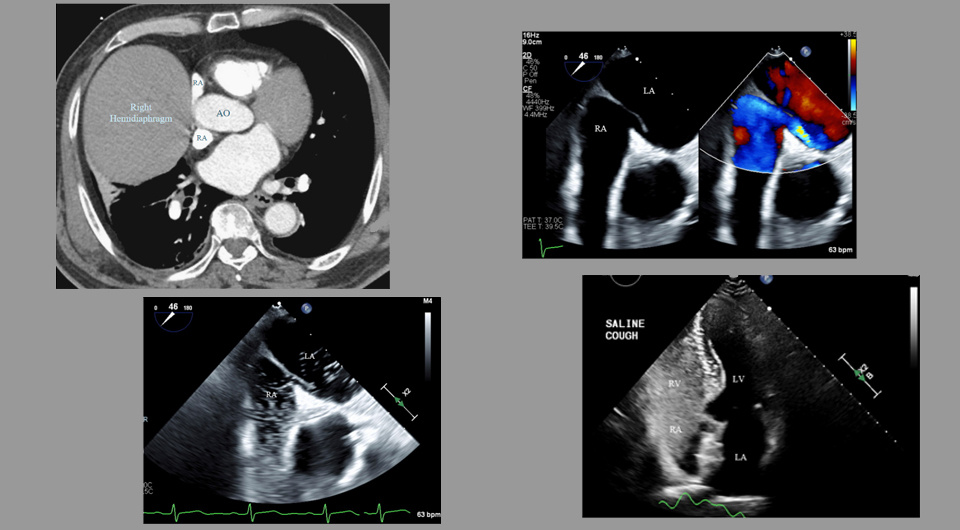

Georg Gussak et al. / BMJ Case Reports, 2025

Эхокардиография в стационаре показала признаки шунта крови на уровне предсердий без дилатации правого желудочка и повышения давления в легочных сосудах. При повторной ревизии КТ грудной клетки врачи отметили деформацию стенки предсердия, непосредственно примыкающей к расширению аорты и правой гемидиафрагме. Рентгеноскопия легких во время дыхания не выявила паралича правой гемидиафрагмы, этиология его высокого положения осталась неустановленной. Катетеризация правых отделов сердца лежа показала нормальное давление в обоих предсердиях и легочных сосудах и отсутствие значимых изменений сатурации в камерах сердца. Отношение объемного кровотока в малом и большом кругах кровообращения составило 0,8, что указывает на наличие шунта слева направо. Чреспищеводная допплерография выявила небольшое расширение левого предсердия, среднего размера открытое овальное окно (врожденный дефект межпредсердной перегородки) и подтвердила наличие умеренного шунта справа налево.